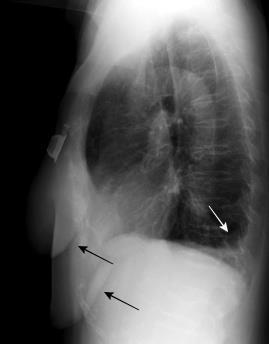

Neumonía por Estrept. neumonía. Derrame pericárdico. Empiema necesitatis (tubo de drenaje)

Edema de los tejidos extrapleurales subcostales (60%, 21 of 35).Takasugi et al. The extrapleural fat in empyema: CT appearance. Br J Radiol 1991